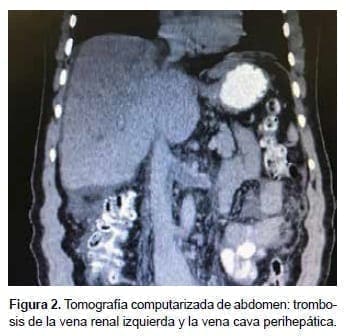

En la endoscopia de vías digestivas altas se observaron várices esofágicas de grado I-II y el ecocardiograma transtorácico fue normal. En la ecografía abdominal, se encontró abundante líquido ascítico libre, hipertrofia del lóbulo caudado, trombosis de las venas hepáticas y un sistema venoso portal normal. La tomografía computarizada abdominal demostró trombosis de la vena cava inferior, las venas hepáticas y la vena renal izquierda (figura 2).